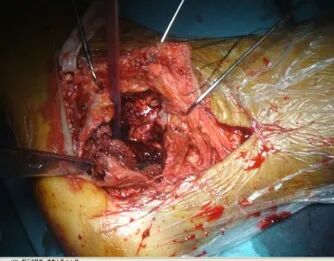

手术刀要一刀见骨,将骨膜连同软组织以及腓骨长短肌肌腱一起向上掀起。

切开皮肤后开始用7号丝线协助牵开

技巧三、克氏针的位置剥离骨膜后,3根克氏针牵开皮肤。注意距骨前后一根,骰骨一根。这样显露充分

骨刀将跟骨外侧壁翻开,同时跟骨内翻即可清晰显露距下关节和跟骨后关节面